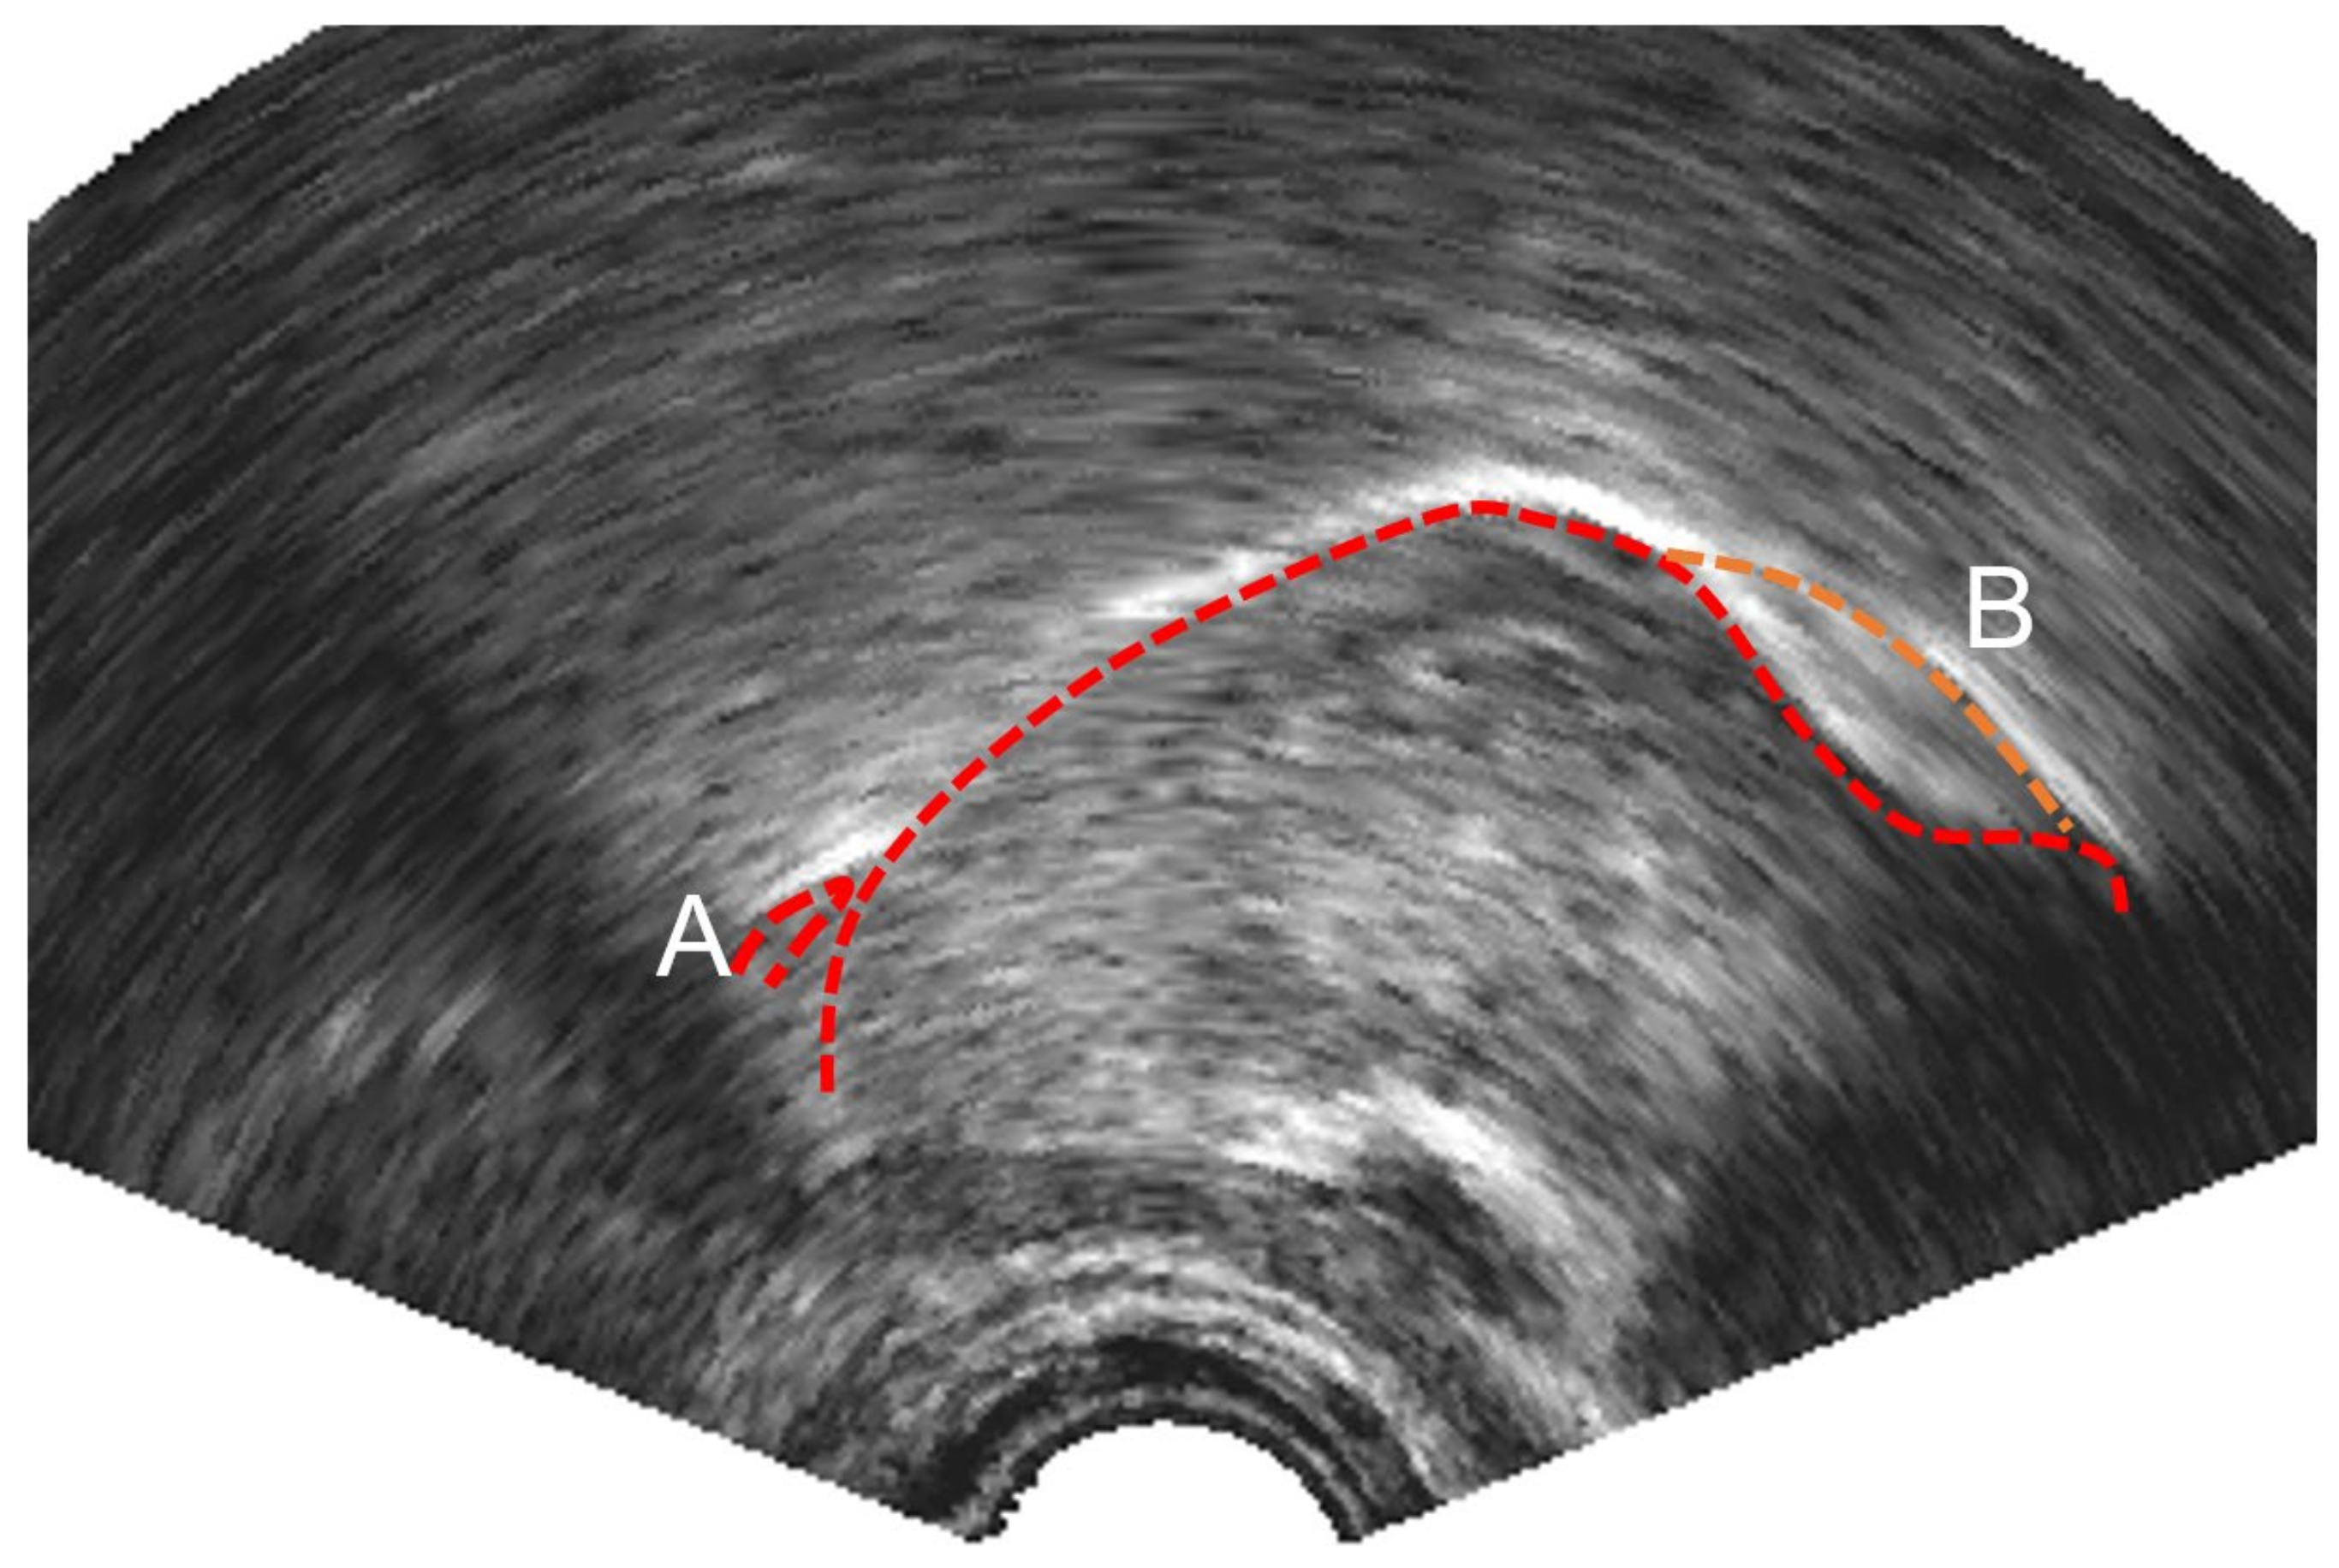

3.1.3. Ultrasound Keypoint Labelling